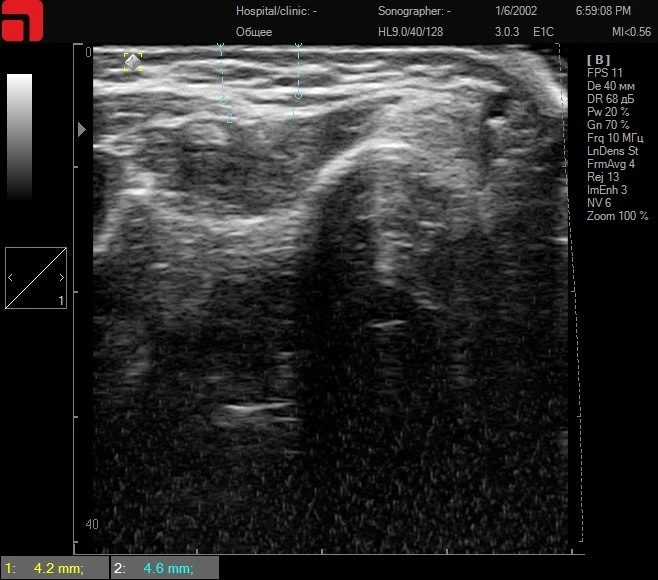

Рис. 1. На снимке отмечается большое количество соединительнотканных септ и трабекул в подкожно-жировой клетчатке, а также выражена фасция, покрывающая СМАС-слой.

Так как мишенями для проведения HIFU SMAS-лифтинга является именно соединительная ткань в подкожно-жировой клетчатке и на SMAS, их высокое содержание обеспечивает яркую выраженность результатов (рис. 1). При проведении HIFU SMAS-лифтинга создаются точки коагуляции в области соединительной ткани, что приводит к сокращению ее площади, укреплению и запуску процессов лифтинга. Проводя ультразвуковую диагностику кожи высокого разрешения, специалист всегда выявляет пациентов с большим количеством соединительной ткани и может с уверенностью назначать им монопроцедуру без подключения дополнительных методов в курсе лечения.

Рис. 2. На сканограмме определяется выраженная соединительная ткань в области подкожно-жировой клетчатки (начинается на глубине от 3 мм), четко дифференцируется соединительная ткань, покрывающая СМАС-слой (глубина 4,6 мм). Противопоказаний к зоне проведения процедуры не выявлено. Основными рабочими датчиками для получения лифтинга будут D4 – 4,5 мм и M7 – 3 мм на аппарате Doublo.